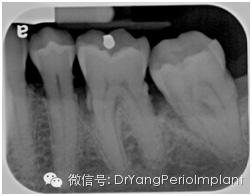

诊断质量欠佳的根尖片(原因:显示太多occlusal table说明片子有变形) X光片取自笔者治疗过的病人)。

要是碰巧根尖片没达到这个标准呢?那要看这是解剖原因造成的(有些患者无法忍受口腔里置放片子,会有恶心反应;或是腭部弧度过小,平坦,片子无法平行于牙长轴),还是拍片技术原因造成的。解剖原因呢只好将就啦,技术原因呢,打回去重拍。